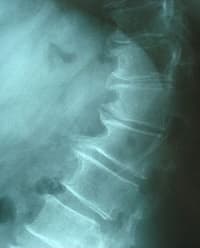

Spondylosis is the degeneration of the vertebral column from any cause. In the more narrow sense it refers to spinal osteoarthritis, the age-related degeneration of the spinal column, which is the most common cause of spondylosis. The degenerative process in osteoarthritis chiefly affects the vertebral bodies, the neural foramina and the facet joints (facet syndrome). If severe, it may cause pressure on the spinal cord or nerve roots with subsequent sensory or motor disturbances, such as pain, paresthesia, imbalance, and muscle weakness in the limbs. When the space between two adjacent vertebrae narrows, compression of a nerve root emerging from the spinal cord may result in radiculopathy (sensory and motor disturbances, such as severe pain in the neck, shoulder, arm, back, or leg, accompanied by muscle weakness). Less commonly, direct pressure on the spinal cord (typically in the cervical spine) may result in myelopathy, characterized by global weakness, gait dysfunction, loss of balance, and loss of bowel or bladder control. The patient may experience shocks (paresthesia) in hands and legs because of nerve compression and lack of blood flow. If vertebrae of the neck are involved it is labelled cervical spondylosis. Lower back spondylosis is labeled lumbar spondylosis. The term is from Ancient Greek σπόνδυλος spóndylos, "a vertebra", in plural "vertebrae – the backbone". In cervical spondylosis, a patient may be presented with dull neck pain with neck stiffness in the initial stages of the disease. As the disease progresses, symptoms related to radiculopathy (due to compression of exiting spinal nerve by narrowed intervertebral foramen) or myelopathy (due to compression on the spinal cord) can occur. Reduced range of motion of the neck is the most frequent objective finding on physical examination. In cervical radiculopathy, there would be numbness, tingling, or burning pain at the skin area supplied by the spinal nerve, shooting pain along the course of the spinal nerve, or weakness or absent tendon reflex of the muscle supplied by the nerve.